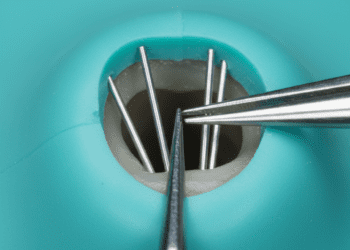

- Mandíbula móvel: Permite abrir e fechar a boca, reproduzindo movimentos naturais.

- Utilização dos instrumentos: Praticar as técnicas com os instrumentos odontológicos reais, como espelhos, pinças, brocas e curetas, desenvolvendo a coordenação manual.